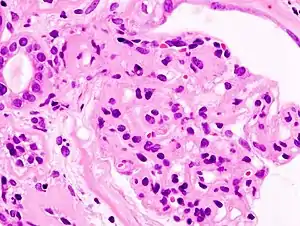

| Microscopic image of diabetic glomerulosclerosis, the main cause of nephrotic syndrome in adults. | |

_PAM.jpg.webp)

Secondary causes of nephrotic syndrome have the same histologic patterns as the primary causes, though they may exhibit some difference suggesting a secondary cause, such as inclusion bodies.[22] They are usually described by the underlying cause.